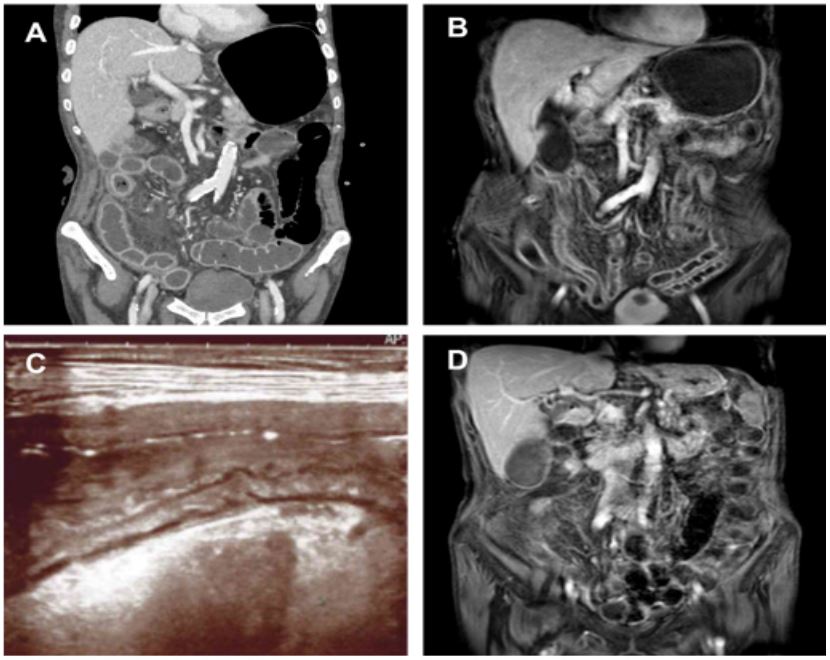

Two weeks after surgery, contrast-enhanced CT scan, and subsequent Enterography Magnetic Resonance Imaging (E-MRI) showed a diffuse ileitis, extending for more than 1 meter from the ileostomy, with continuous hyperenhanced thickening of the mucosa and submucosa layers up to 6-7 mm, and several lymphadenopathies. An initial loss of the clear stratification of the intestinal wall, with a greater hyperechoic submucosal component was detected at intestinal ultrasound (Figure 1, panels A-C).

E-MRI showed a significant improvement of the previous pan-enteritis (Figure 1, panel D). Endoscopy showed the persistency of solely erythematous patches and microulcerations limited to the distal ileal tract (Figure 2, panel B). A persistent moderate inflammatory infiltrate in the lamina propria and pseudoatrophy of the villi was highlighted at the pathological re-evaluation (Figure 3, panels C-D). Given the good response, maintenance treatment was continued with SC ustekinumab (90 mg/8 weeks).

Figure 1: Panel A, B and C before ustekinumab, panel D after 2 administrations of ustekinumab. Thickening and hyperenhancement of the luminal layers and several lymphadenopathies in the arterial phase at the abdominal CE-CT scan (panel A). Thickening and hyperintensity of the small bowel walls in the THRIVE MRI sequences (panel B). Intestinal ultrasound with evidence of greater representation of the hyperechoic submucosal layer and initial loss of the normal stratification of the intestinal wall (panel C). Reduced thickening and intensity of the small bowel walls in the THRIVE MRI sequences (panel D). CE-CT: Contrast-Enhanced Computed Tomography scan; MRI: Magnetic Resonance Imaging.